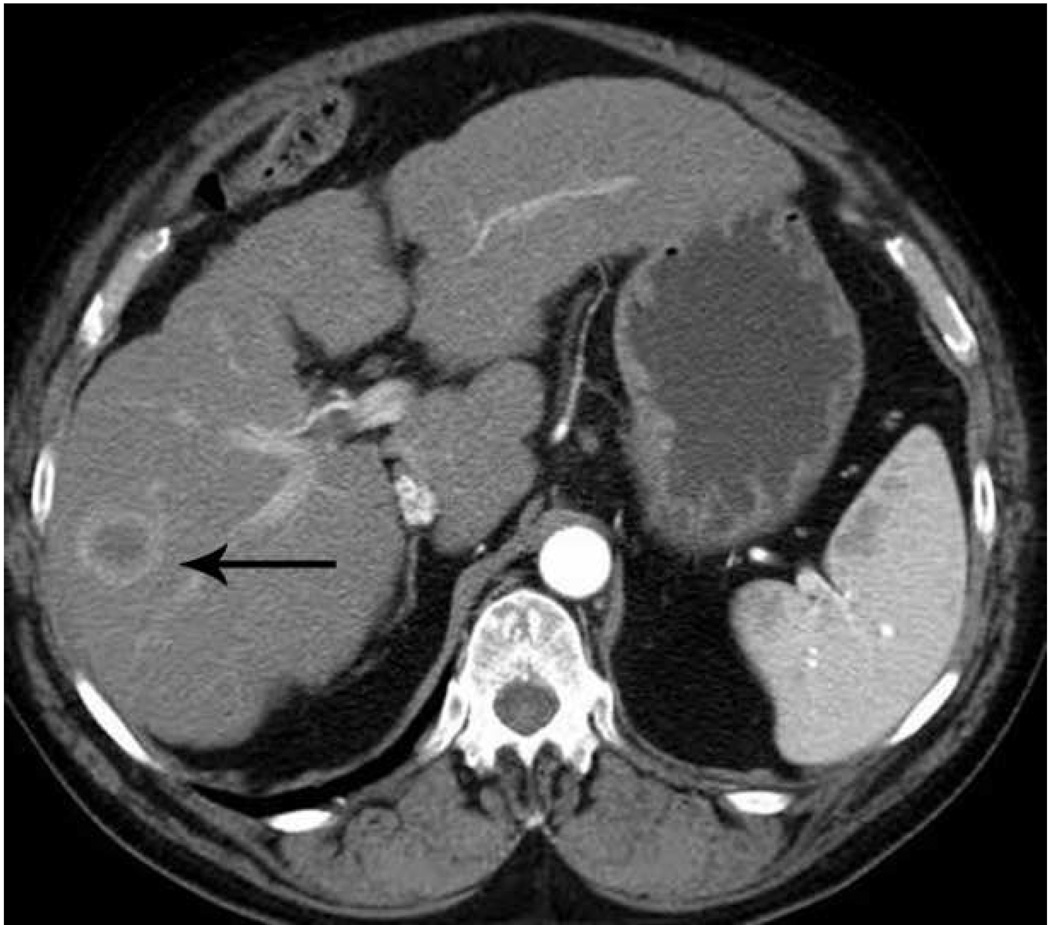

In Europe, the Acculis Microwave Tissue Ablation system consists of a 2.45 GHz generator, with power output settings ranging from 30–100 W, and a percutaneous 15-gauge cooled antenna. The HS Amica microwave system uses a 2.45 GHz generator, with power output to 100 W (60 W recommended output) through 14-gauge and 17-gauge water cooled applicators (Figure 10).

Figure 10.

Microwave ablation performed with HS Amica System. Pre-procedure CT demonstrates nodular arterially enhancing lesion in the posterior right hepatic lobe (arrow, a), redemonstrated on contrast enhanced pre-procedure ultrasound (b). Three sequential placements were performed with an antenna powered at 60 W for 15 minutes each. This produced an ablation zone nearly 7 cm in maximal diameter, as seen on post procedure US (c) and CT (arrow, d). Case courtesy of Drs M. Franca Meloni and Anita Andreano, University of Milan-Bicocca.